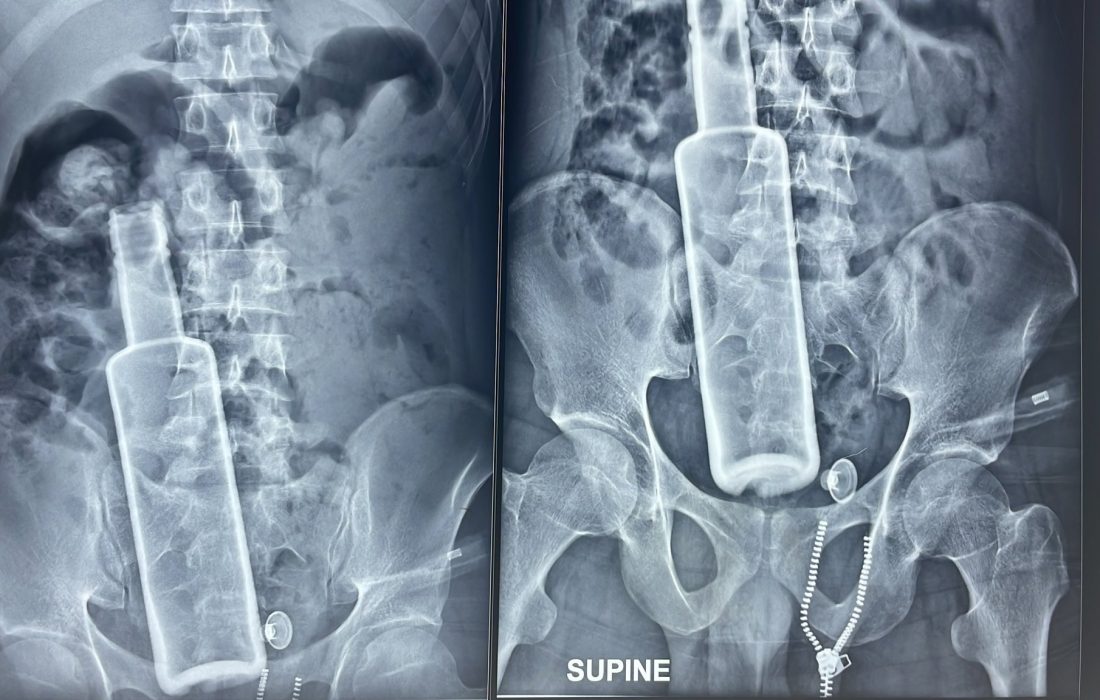

रौतहटको चन्द्रनिगाहपुरबाट ल्याइएका बिरामीको नाडीको चाल १२० भन्दा माथि पुगेको थियो। पेट फुलेर ठूलो भएको थियो। बिरामीसँग आएका व्यक्तिको साथमा रहेको एक्सरे रिपोर्ट डाक्टरलाई नै तर्साउने खालको थियो।

एक्सरेमा उनको पेटमा एउटा सिंगो बोतल देखिन्थ्यो।

बिहान साढे ६ बजेतिरबाट बिरामीको शल्यक्रिया सुरू गरिएको थियो। बोतलको आधा भाग पेटभित्र र आधा भाग ठूलो आन्द्राभित्रै रहेको देखियो। बोतलको टुप्पो आन्द्रा फुटालेर बाहिर निस्किएको थियो। पेटभित्र दिसा फैलिएर आन्द्राहरू सबै सुन्निइसकेका थिए। बोतलमा बिर्को थिएन। भित्र केही दिसा र रगत पसेको थियो।

एक्सरे गर्दा रिपोर्टमा पेटभित्र रक्सीको सिंगो बोतल देखिएपछि चिकित्सकले उनलाई तुरून्तै रेफर गरे। आफन्तले उनलाई बाराको नौतन गण्डकस्थित एलएस न्युरो अस्पताल पुर्याए। शल्यक्रिया गर्नुपर्छ, ज्यानको खतरा पनि हुनसक्छ भनेपछि भरतपुर ल्याइएको थियो।